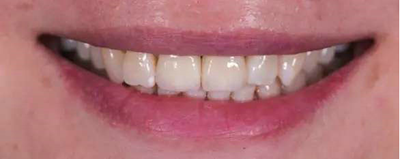

修復(fù)后

本病例中通過對(duì)患者修復(fù)體佩戴后的舌側(cè)、頰側(cè)、左側(cè)、右側(cè)以及微笑照的采集,充分展示修復(fù)體在口內(nèi)的佩戴情況,可以看到無論顏色還是與鄰牙的匹配適宜度都是非常高,也比較吻合年輕女性對(duì)美觀的要求。同時(shí),通過術(shù)后多次隨訪及跟蹤患者后期使用狀況,患者也對(duì)修復(fù)效果十分滿意。